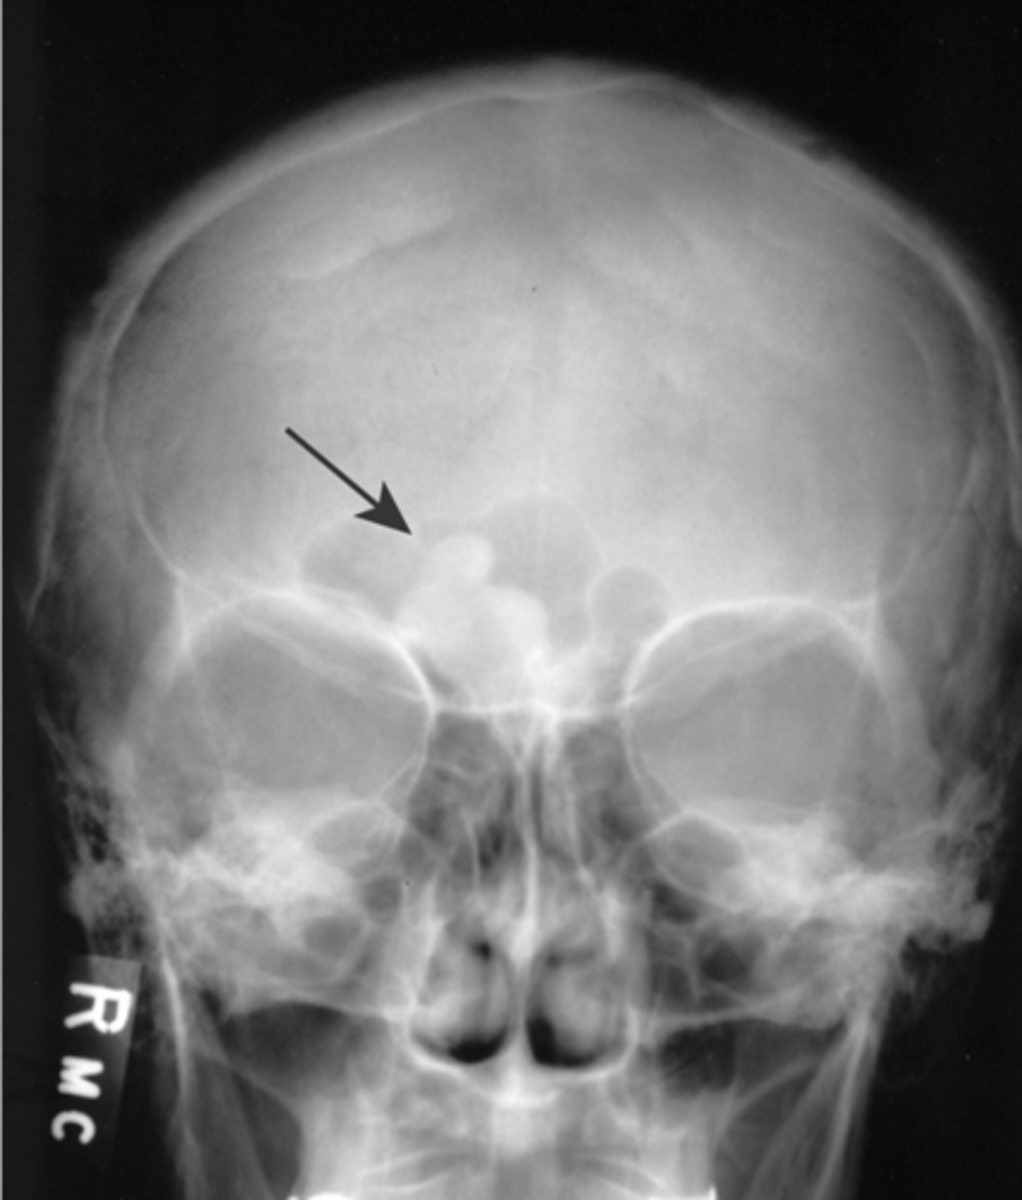

Beveled edge

ID radiographic feature of eosinophilic granuloma in the skull

Button sequestrum

ID radiographic feature of eosinophilic granuloma in the skull